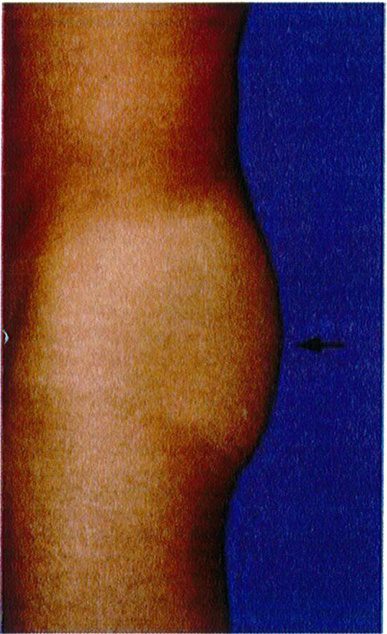

Hai điểm bám cuối cùng của cơ mông phải được đánh giá là ‘khớp nối’ mặt dưới ngoài mông với đùi và ‘khớp nối’ vùng giữa ngoài mông với mặt ngoài đùi. Nếu lý tưởng (Hình 24 và 25), bờ các cơ vùng mông có thể không xác định được vì chúng nối liên tục với khu- ng, thống nhất thành 1 khối. Tuy nhiên, ở một số bệnh nhân, phần bờ ngoài của khối cơ lại xác định được rõ ràng, tạo ra một đường lõm không thẩm mỹ.

Các vùng chuyển tiếp này nên được đánh giá và phân loại là chuyển tiếp liên tục (không thấy mép cơ), vừa phải (đường ranh giới chúng tạo ra không rõ nét), và không liên tục (đường ranh giới rõ nét) (xem hình 24 và 25). Khi sự phân tách này ngày một rõ, nên xem xét để tiêm lipofiller giúp đường chuyển tiếp trở nên liên tục.

Smooth transition: Chuyến tiêp liên tục Moderate demarcation: Trung gian Sharp demarcation: Không liên tục

Hình. 25. Đánh giá vùng chuyển tiếp giữa mặt giữa ngoài mông và hông (mũi tên đen). Vùng chuyển tiếp liên tục được coi là lý tưởng. Các vùng chuyển tiếp khác có thể là trung gian hoặc không liên tục (hình giữa và bên phải). Ở cả 3 bệnh nhân này, điểm C đều không có dấu hiệu lõm.

Smooth transition: Chuyển tiếp liên tục Moderate demarcation: Trung gian Sharp demarcation: Không liên tục